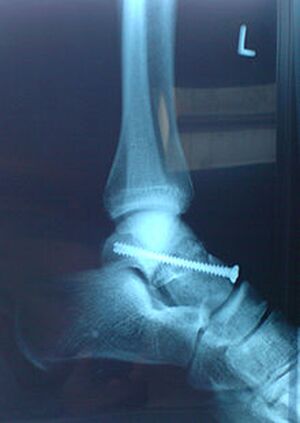

Bandverletzungen im Sprunggelenk

Das sind häufige Verletzungen im Sport.

Im Fußball können Zerreißungen der Außenbänder vor allem nach einem Tritt des Gegners gegen den Knöchel oder durch Umknicken bei der Landung nach einem Kopfball auftreten. Dabei überschreitet das ungeschützte Gelenk die Kippgrenze, der Muskel reagiert nicht schnell genug. Besonders ein übermüdeter und ungenügend aufgewärmter Muskel ist aufgrund seines herabgesetzten Reaktionsvermögens besonders gefährdet.

Bei Außenbandrissen im Bereich des Sprunggelenkes wird immer öfter ohne Operation behandelt. Nach Verschwinden der Schwellung erhält der Betroffene eine Plastikschiene, mit welcher der Fuß im Sportschuh nahezu wieder normal belastet werden kann. Bis zur völligen Ausheilung vergehen einige Wochen. Der Heilungsprozess kann durch Bewegungs- und Dehnübungen, sowie durch gezielte Elektrotherapie wesentlich unterstützt werden.

Bei Komplettabrissen und in speziellen Fällen ist meist eine Operation notwendig.